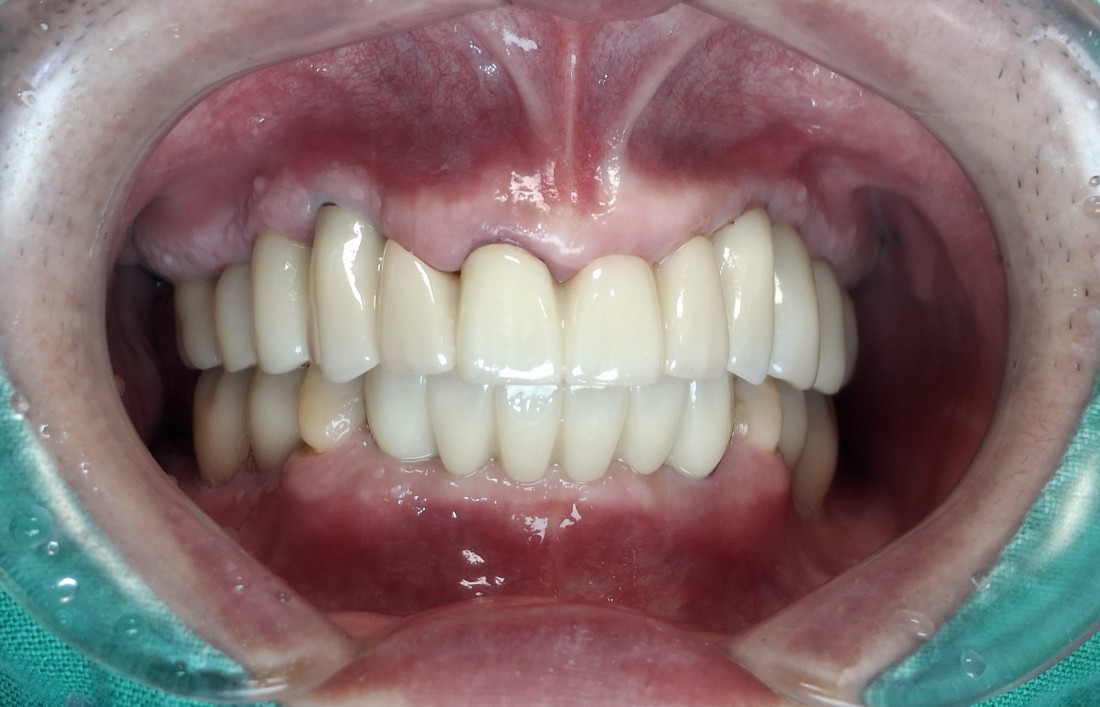

수완동 임플란트 치과는

자체 치아기공소를 운영하고 있습니다.

대표원장인 제가 직접

치아기공소의 보철물 퀄리티를

관리하고 있기 때문에,

무엇보다도

< 예쁘게, 잘 씹어지는 >

수완동 임플란트를 약속드릴 수 있습니다.

잘 관리하면 반영구적으로 사용할 수 있는

임플란트이기 때문에

특히 자연치아보다 더 자연스러운

아름다운 임플란트를 완성하는

수완동 임플란트 치과입니다.